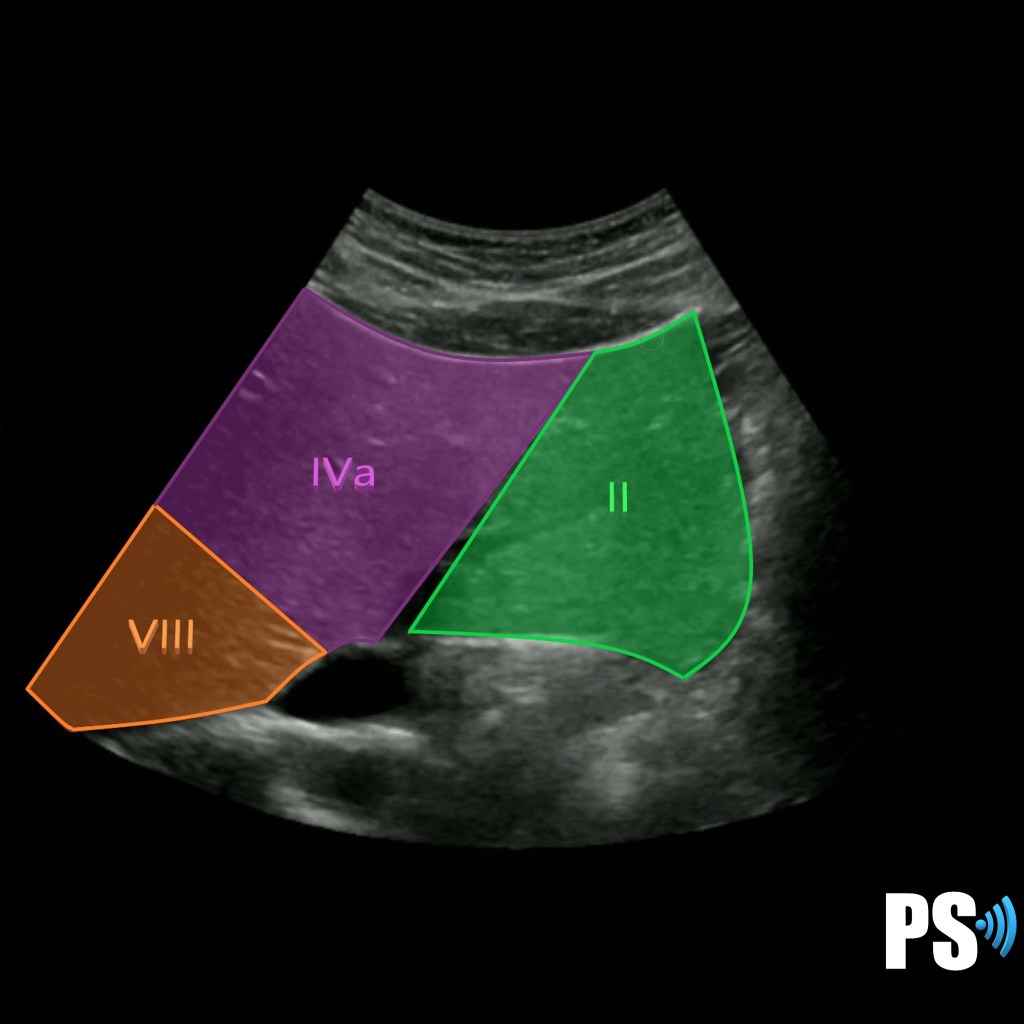

Transverse Left lobe Hepatic veins

Segments II, IVa and VII